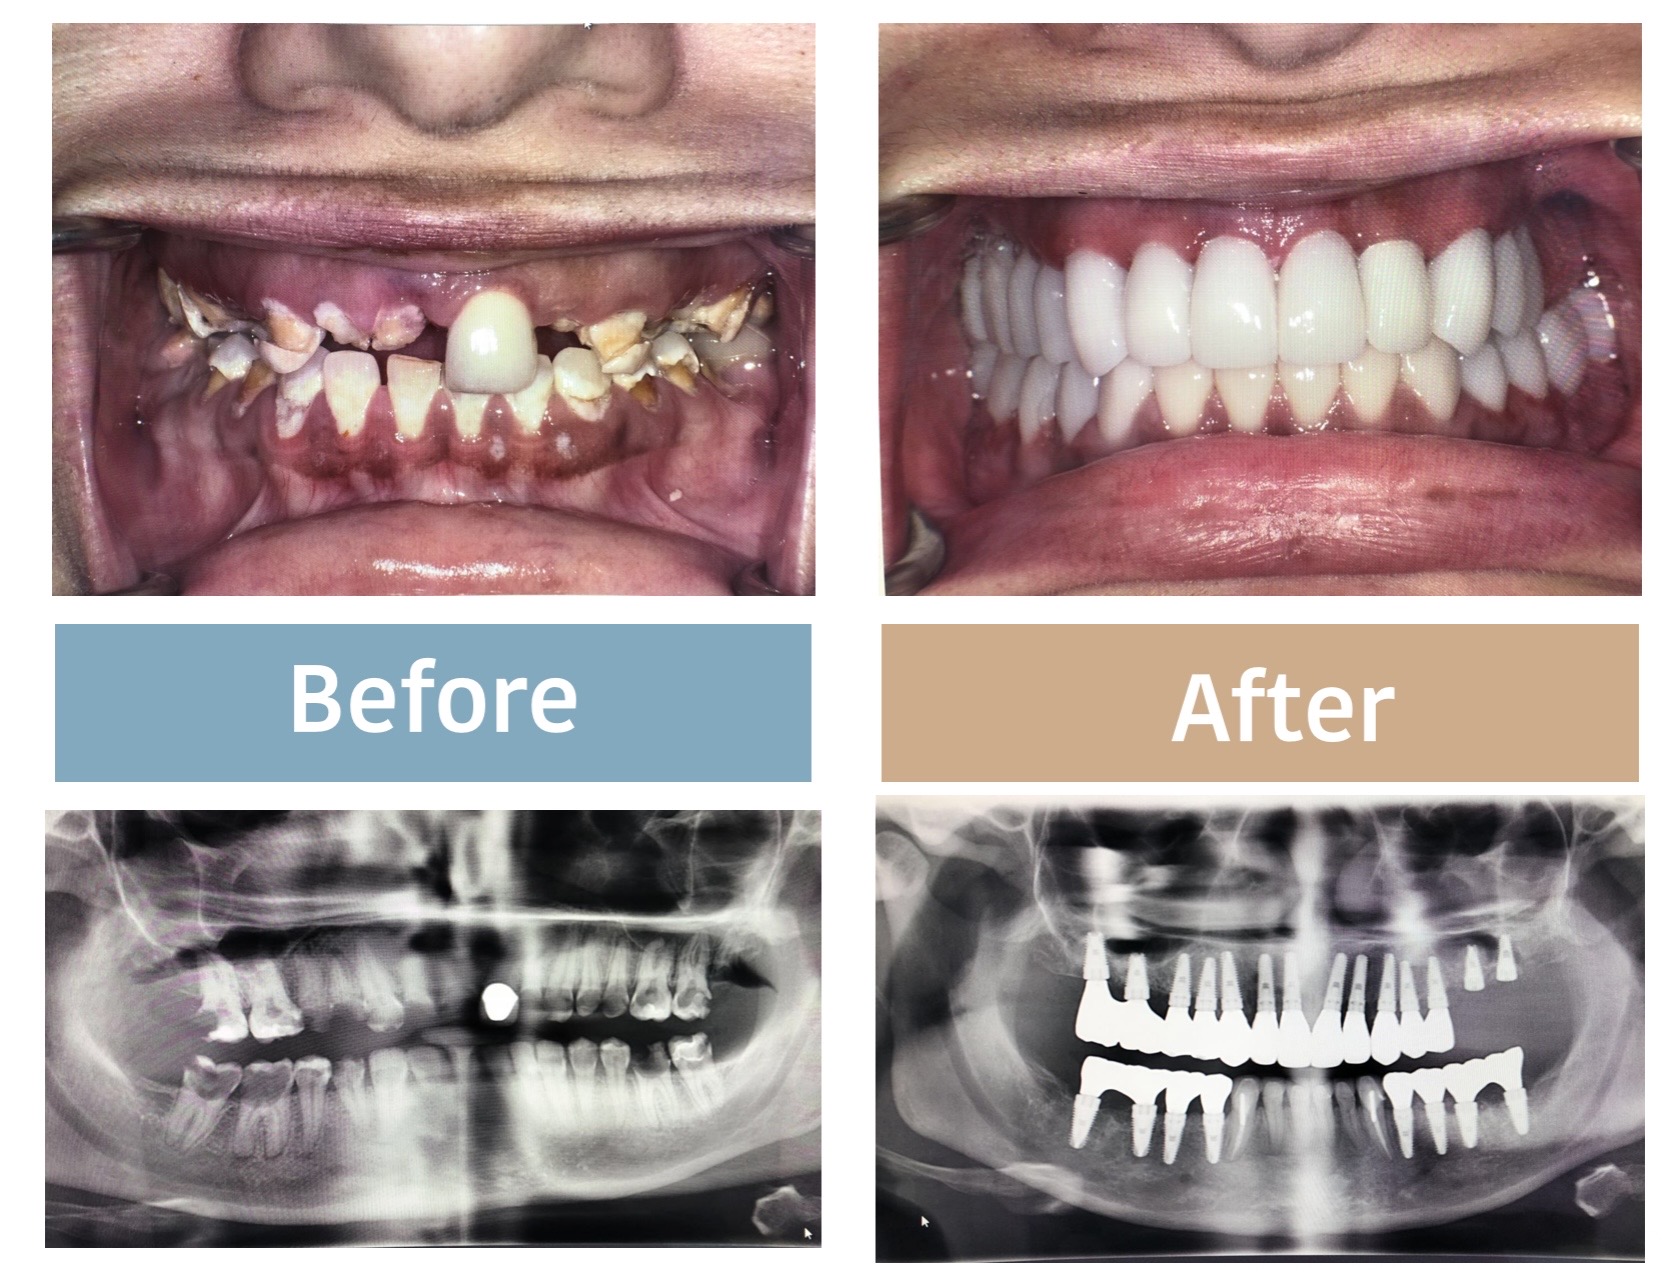

陳博士拉斯維加斯學生的案例分享!

陳博士有一位學生在拉斯維加斯擁有6間診所。

過去,他只要遇到有植牙的案例就會轉給陳博士處理,他起初不想學植牙,

因為他覺得植牙風險太大,但陳博士鼓勵他:「醫療一直在進步,不要被自己侷限了。」

這位醫師自從上了陳博士的課程,2個月之後在自家診所,完成了他第一個全口植牙案例(圖)。

陳博士非常替他開心,從排斥、不想植牙的醫師,到現在能親手完成全口漂亮的植牙手術。

這位牙醫師至今已經在拉斯維加斯開業10多年了,只要願意相信踏出一步,信心與專業都能快速成長!